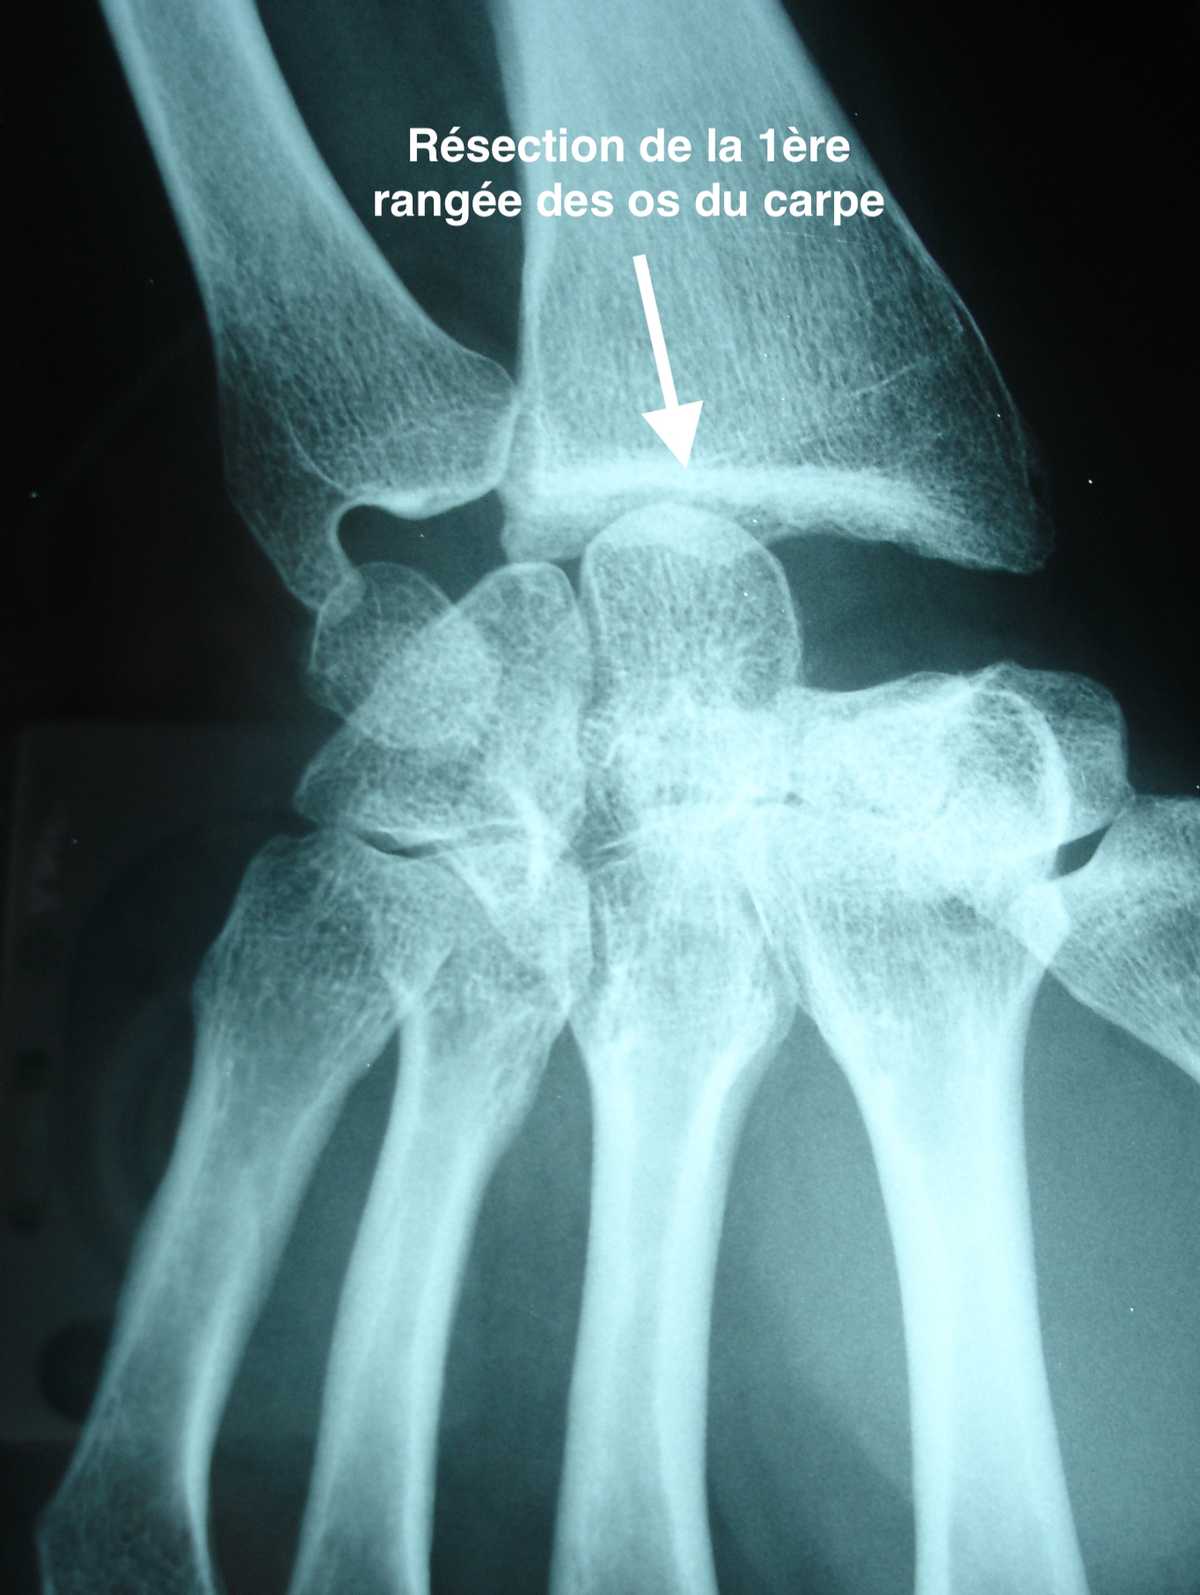

Résection de la 1ère rangée des os du carpe

La résection de la 1ère rangée des os du carpe consiste à enlever le lunatum ainsi que les 2 os adjacents, le scaphoïde et le triquetrum.

L’os situé sous le lunatum, appelé capitatum, vient alors s’articuler avec le radius.

Faite suffisamment tôt, cette intervention permet de conserver un poignet fonctionnel et de reprendre la plupart des activités habituelles, avec une nette amélioration des douleurs, au prix d’une perte partielle de la mobilité en flexion et extension, et parfois d’une perte de la force de serrage.

Il n’y a pas de conséquence esthétique à cette intervention.